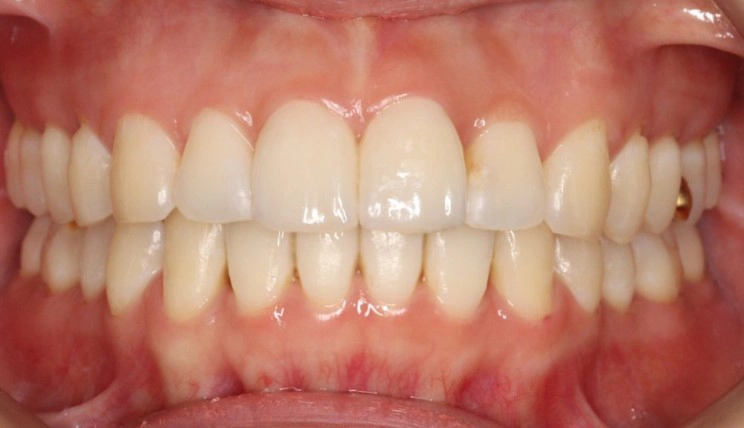

Crowding

Crowding is the condition in which there is a discrepancy between tooth size and space available for the teeth to be aligned in the dental arch

Patient Information:

Age: 17

Gender: female

Invisalign Treatment Option: Invisalign Comprehensive

Total Treatment Time:

29 months